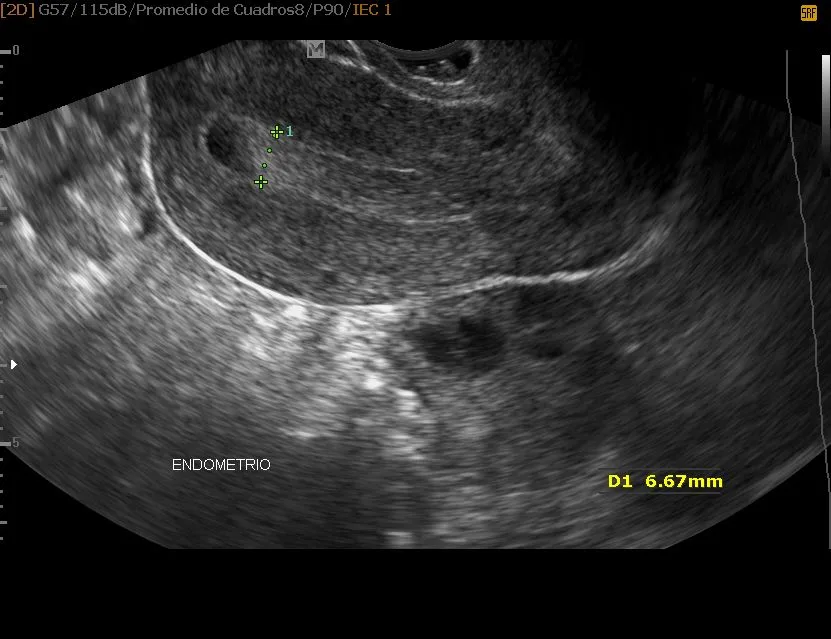

SONOHISTEROSALPINGOGRAFIA

Este estudio consigue una evaluación más detallada del endometrio, lo que permite evaluar la presencia de masas endometriales (miomas o pólipos) o adherencias y medir con más exactitud el espesor endometrial (de mucho valor en pacientes postmenopaúsicas con sangrado vaginal). Se realiza mediante una exploración transabdominal en la que inicialmente se buscan masas que pudieran estar fuera del campo de visión durante el ultrasonido transvaginal y después se inyecta lentamente la solución salina estéril a través del catéter bajo control ultrasonográfico continuo.